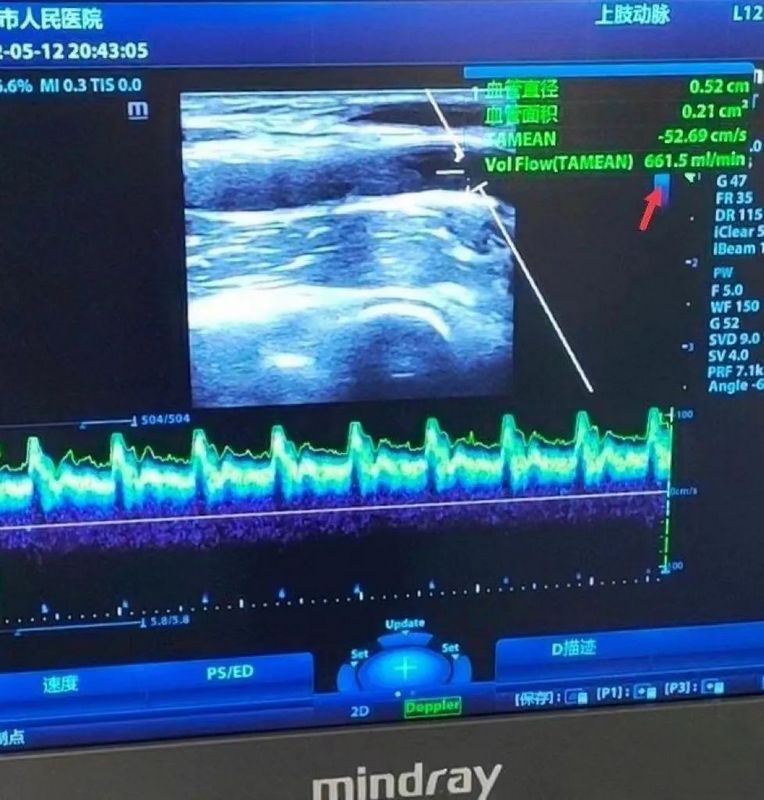

患者某某來我院就診時(shí),時(shí)間已遠(yuǎn)遠(yuǎn)超過36h,彩超下顯示患者內(nèi)瘺血管管腔有大量血栓形成。

經(jīng)過2天的不懈努力,患者的內(nèi)瘺血栓,彩超下顯示基本消失。內(nèi)瘺血流量達(dá)到600ml/min以上,患者內(nèi)瘺恢復(fù)正常。